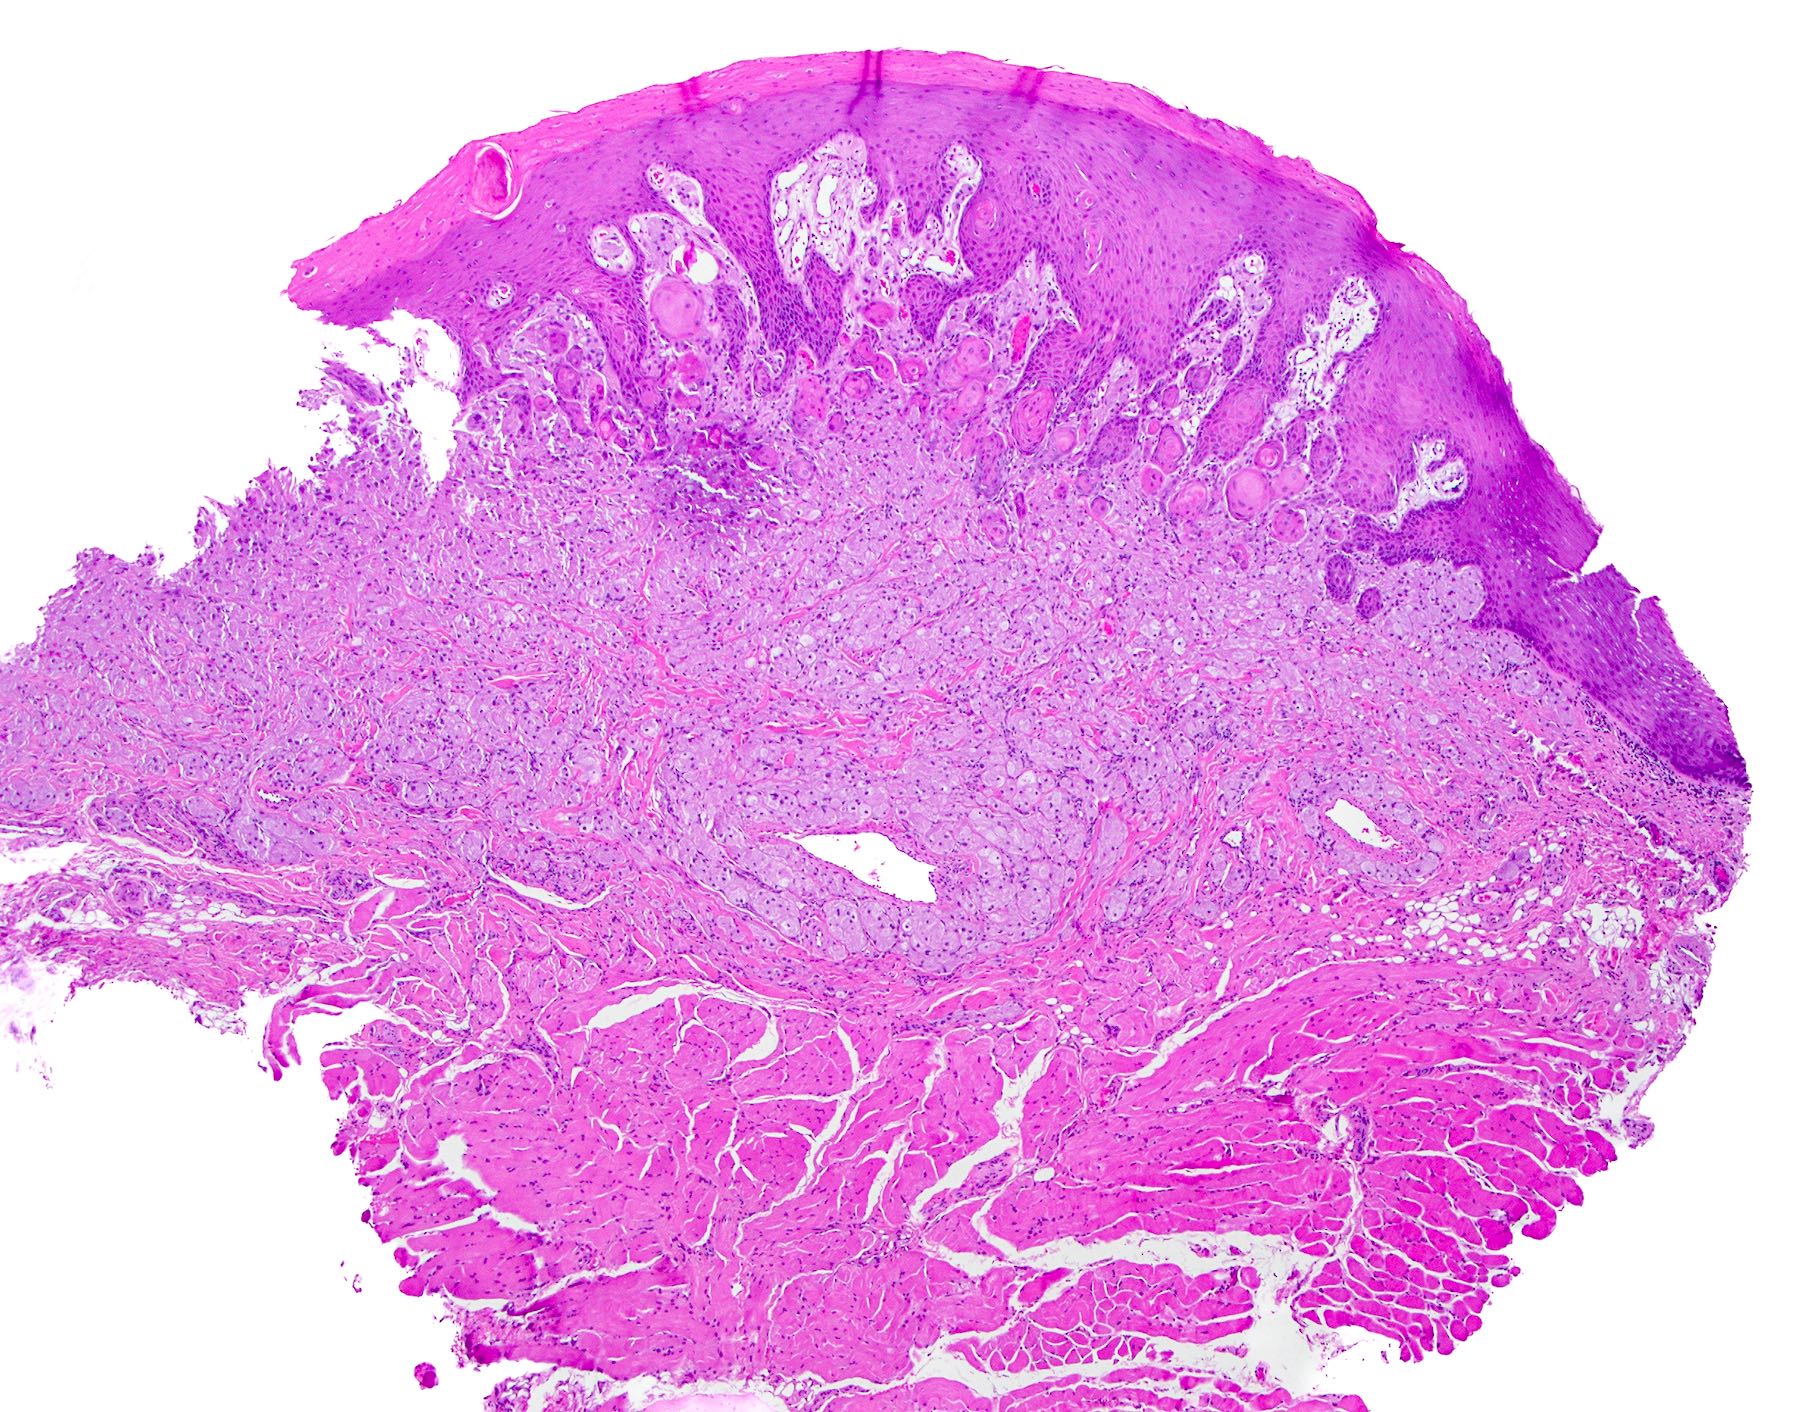

• Thick elongation of the overlying epithelium with bulbous or sometimes jagged / sharp, interconnecting rete ridges (Am J Dermatopathol 2011;33:112)

• May exhibit keratin pearl formation: concentric layers of keratinocytes with central keratinization (Am J Dermatopathol 2011;33:112)

• Lacks significant nuclear atypia; although mitotic figures may be seen, they are not numerous or atypical (Am J Dermatopathol 2011;33:112)

• Awareness of microscopic features seen in conditions / tumors associated with PEH is paramount for proper diagnosis

• Replacement of underlying fibrous stroma with sheets of pale, basophilic, plump granular cells suggests that the overlying epithelial proliferation is likely associated with granular cell tumor

PEH in granular cell tumor PEH in granular cell tumor

PEH in granular cell tumor

Practice question #2

A patient presents with a yellow nodule on the tongue. What is the diagnosis?

1. Frictional keratosis

2. Granular cell tumor with overlying pseudoepitheliomatous hyperplasia

3. Squamous cell carcinoma

4. Verrucous carcinoma

Practice answer #2

B. Granular cell tumor with overlying pseudoepitheliomatous hyperplasia (PEH). Microscopic sections show a dome shaped mass of pale, basophilic, plump granular cells surfaced by hyperkeratotic and hyperplastic epithelium. Although the rete ridges are significantly proliferative and demonstrate keratin pearls, overt cytologic atypia is not appreciated. This proliferative pattern of the epithelium is termed pseudoepitheliomatous hyperplasia and is known to be associated with granular cell tumors. Answer A is incorrect because although there is a thickened layer of parakeratin, this answer choice ignores the replacement of the fibrous stroma by plump granular cells. Answer C, a common pitfall in the diagnosis of this tumor, is incorrect because although the epithelium is proliferative, prominent cytologic atypia is not appreciated. The pathologist must be keen in recognizing the underlying replacement of the fibrous stroma with plump granular cells and must know that granular cell tumors characteristically show PEH in many cases. Answer D is incorrect because verrucous carcinoma would show keratin clefting and prominent, bulbous, plunging rete ridges that push into the underlying muscle.